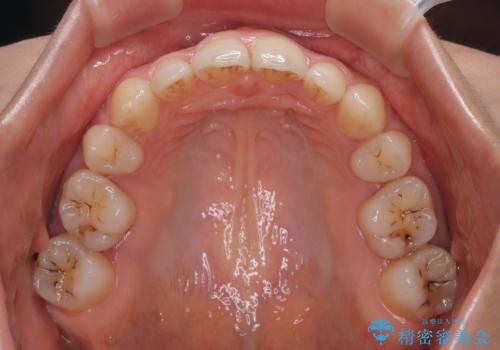

欠損や残存乳歯、深い咬み合わせ ワイヤー矯正で咬合改善

- 後続永久歯の欠損によるスペースと残存乳歯、深い咬み合わせを気にして来院された患者様です。

乳歯を残し、欠損部位のスペースを適正な幅に拡大し、インプラント補綴治療により歯列を整える治療も考えられましたが、ご本人から飛び出している前歯をどうしても引っ込めたいとの要望があったため、残存乳歯ならびに上顎左右第二小臼歯を抜歯して、歯列を整えることとしました。

上下臼歯の咬み合わせ改善には補助装置を、深い咬み合わせ改善にはユーティリティーアーチを活用し、ワイヤー装置にて矯正治療を行うこととしました。